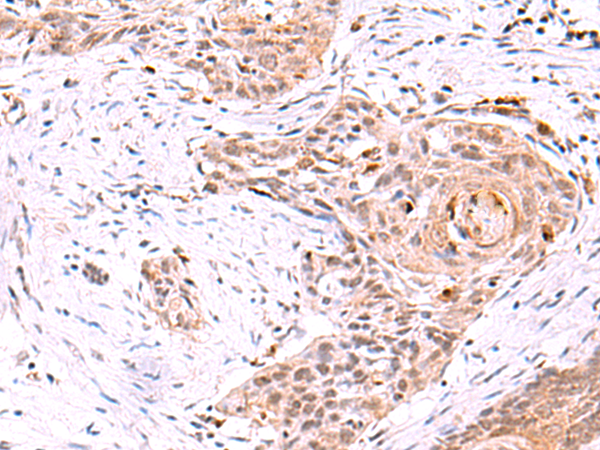

分类: 科研抗体货号: P13568别名:应用: WB,IHC反应种属: Human